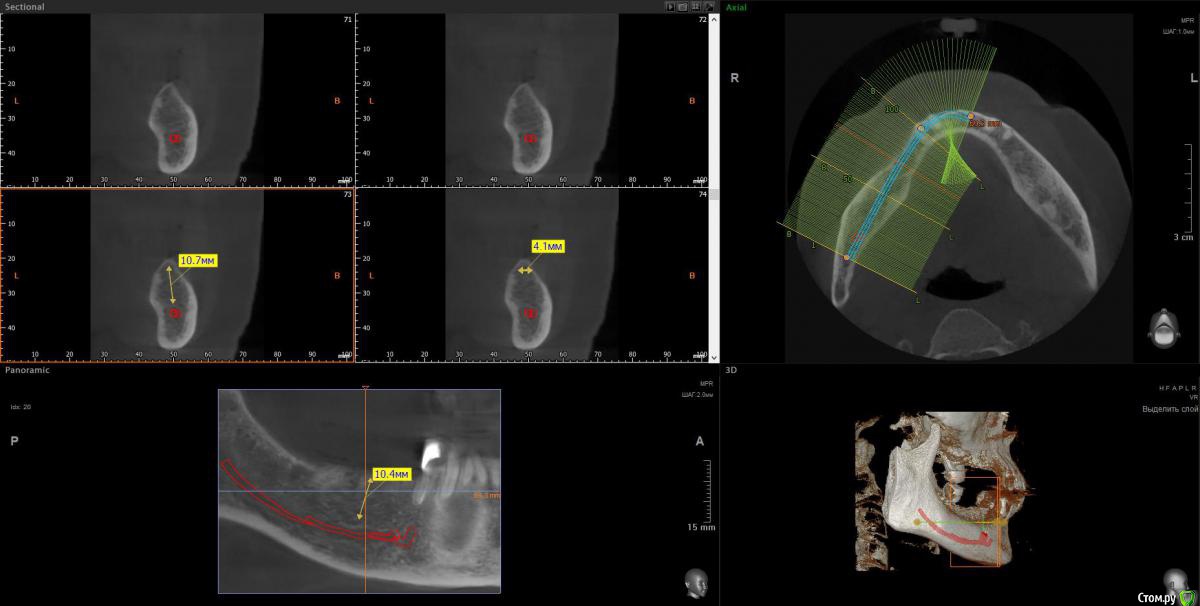

wladdX Опубликовано 11 апреля, 2018 Поделиться Опубликовано 11 апреля, 2018 (изменено) 3-й квадрант Изменено 11 апреля, 2018 пользователем wladdX 1 Ссылка на комментарий

Bier Опубликовано 11 апреля, 2018 Поделиться Опубликовано 11 апреля, 2018 ну да, последний зуб слева я бы удалил. итого 4 имплантата, синуслифтинг на в/челюсти после санации пазухи. 3 Ссылка на комментарий

Irouil Опубликовано 11 апреля, 2018 Поделиться Опубликовано 11 апреля, 2018 (изменено) Про нижнюю челюсть, слева. Левую пазуху В ЛЮБОМ СЛУЧАЕ надо оперировать. P.S. я тут так свободно про тотальное протезирование на верхней челюсти говорю, но у Вас же там передние зубы есть, простите, проглядел. Надо их состояние посмотреть, если в порядке то рассмотрите вариант который Олег Юрьевич описал - по два имплантата со стороны и мосты на них. Да, нужны будут синус лифты, но это высоко предсказуемые операции Изменено 11 апреля, 2018 пользователем Irouil Ссылка на комментарий

Bier Опубликовано 11 апреля, 2018 Поделиться Опубликовано 11 апреля, 2018 Добрый день! Искренняя Вам всем благодарность! По поводу удаления последнего зуба слева- это про верхнюю или нижнюю челюсть? Очень заинтересовал метод:все на 4 как возможность обойти пазухи и обойтись без эндоскопической операции,тем более,гаймориты меня не беспокоят.Отпишитесь,плиз,про метод:все на 4.С нетерпением буду ждать Ваших ответов!Для все на 4х придется удалить все оставшиеся зубы. А пазуху в любом случае нужно оперировать. Ссылка на комментарий